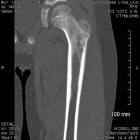

7 year old male c/o limp

Zoom image: Radiological image Radiological image.